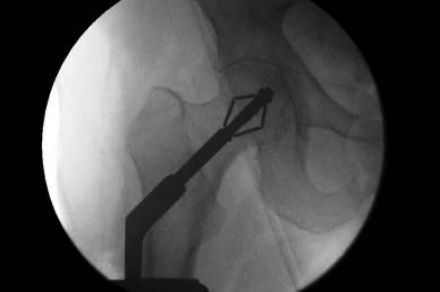

取得認可後,他位於都柏林市的X-Bolt Orthopaedics公司,將可能被整形裝置大廠併購。他解釋:「X螺栓採用可擴張式螺栓,減少骨盆骨折病患的併發症,也降低延長住院的天數(平均每20人就有1人需延長住院日數)。」某天他看到了家中電視是用擴張螺栓固定在牆上,他突然靈機一動,才發明了X螺栓。

他表示,現有的骨盆治療方式採用的是螺絲,但有5%的失敗案例,導致住院日數增加且成本升高。X螺栓的價值在於「減少併發症與平均住院天數,加速手術次數,且價格同於或低於目前市場主要的骨盆治療法。」

點閱影片連結觀看X螺栓的操作方式: https://youtu.be/d5rQKGtzVLE